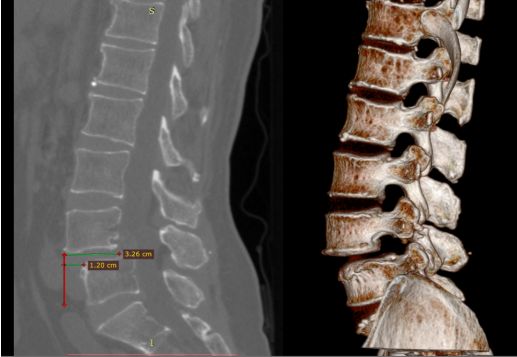

术前CT

术前CT提示腰4椎体向前滑脱,幅度超过椎体横径1/3,为II度滑脱。